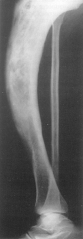

Se localizeaza la oasele lungi, cel mai frecvent la tibie, femur, humerus.

Radiologic, chistul se prezinta ca o zona de osteoliza unica localizata la metafiza proximala a oaselor amintite. Are o forma ovalara, rar cu septe în interior. Zona de osteoliza subtiaza corticala, are contur net si se opreste la cartilajul de crestere. Evolutia este lenta. Descoperirea este întâmplatoare de multe ori cu ocazia unei fracturi la traumatism minim. Chistul osos fracturat se consolideaza normal.

Diagnosticul diferential al chistului osos trebuie facut pe radiografii succesive la diferite intervale cu: condromul osos (se dezvolta mai frecvent pe oasele mâinii si ale picioarelor), echinococoza osoasa (este rara, se localizeaza în diafiza oaselor lungi), tumora cu mieloplaxe (prezinta numeroase septe, se localizeaza epifizar), granulomul eozinofil, gomele sifilitice, abcesul Brodie, osteita chistica, etc.